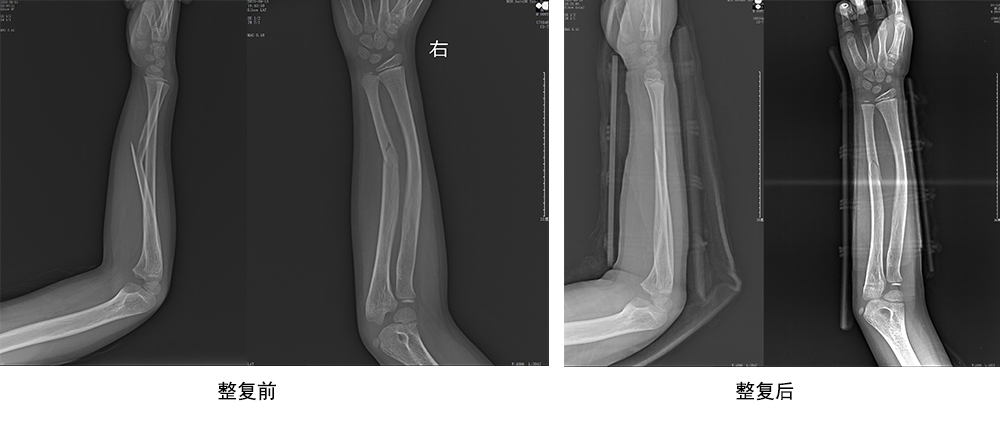

傳統(tǒng)手法整復(fù)病例影像

CR103119